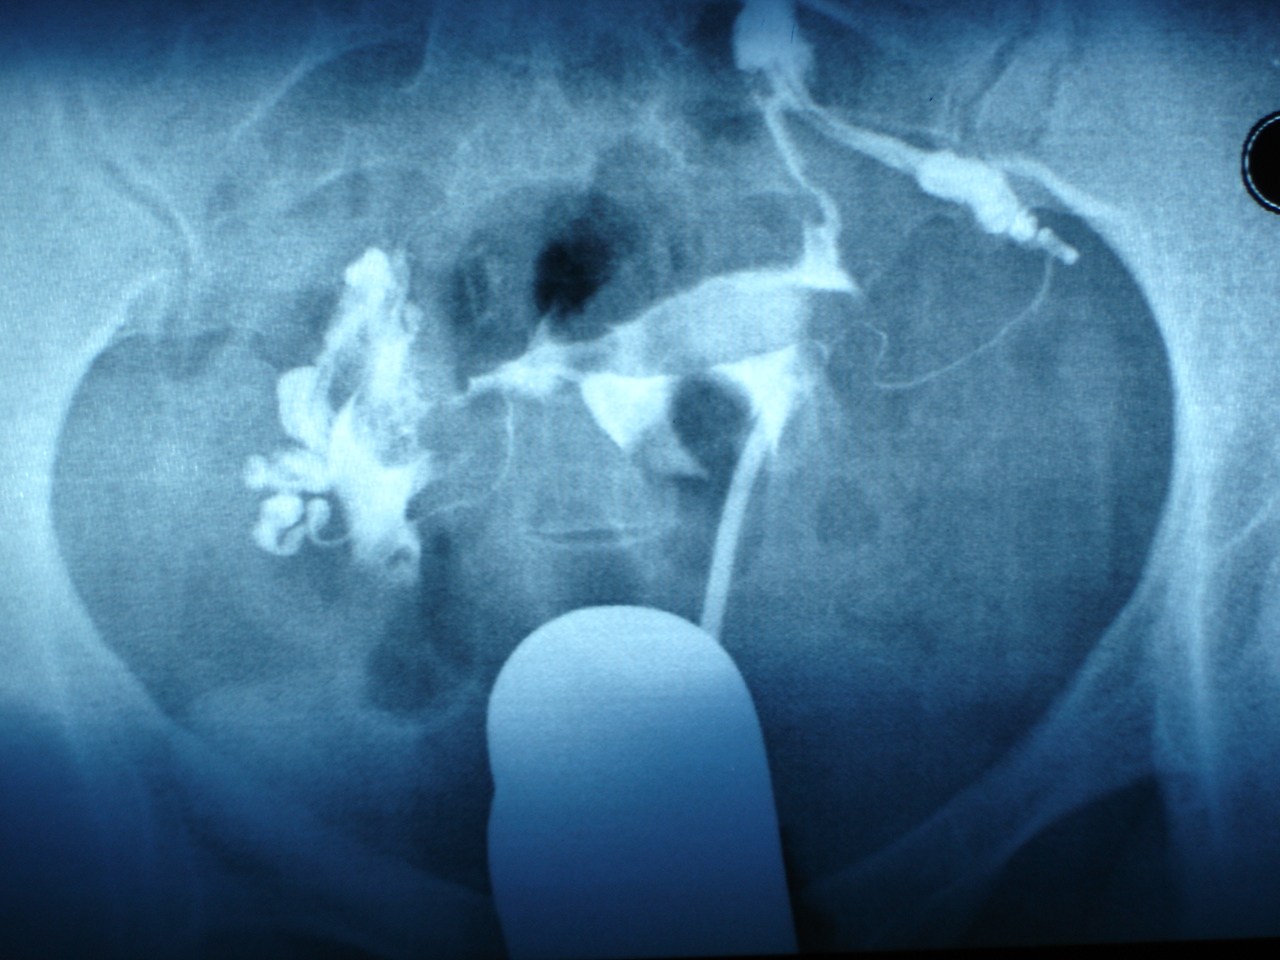

女科医话 - 庞震苗教授中药治疗输卵管积液型不孕一例_mm_卵巢_诊断

图片尺寸600x770